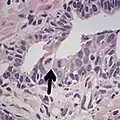

• Collagenous micronodules[4]

• Glomerulations,[4] epithelial proliferations into one or more gland lumina, typically a cribriform tuft with a single attachment to the gland wall.[18]

• Perineural invasion.[4] It should be circumferential[18][notes 5]

• Angiolymphatic invasion[4]

• Extraprostatic extension [4]